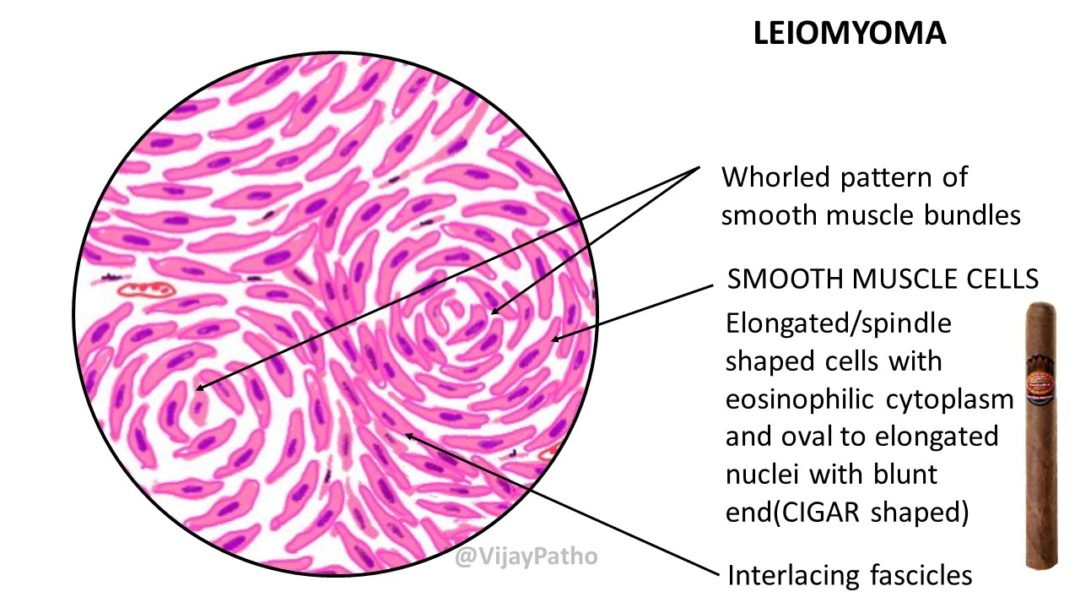

Pathology Of Uterine Leiomyoma - Pathology Made Simple

ilovepathology.com

ilovepathology.com

leiomyoma uterine pathology microscopic cellular dissecting leiomyomas variants mitotically bizzare nuclei epithelioid lipomatous myxoid hydropic include ilovepathology

Pathology Of Uterine Leiomyoma - Pathology Made Simple

ilovepathology.com

ilovepathology.com

leiomyoma pathology uterine parasitic